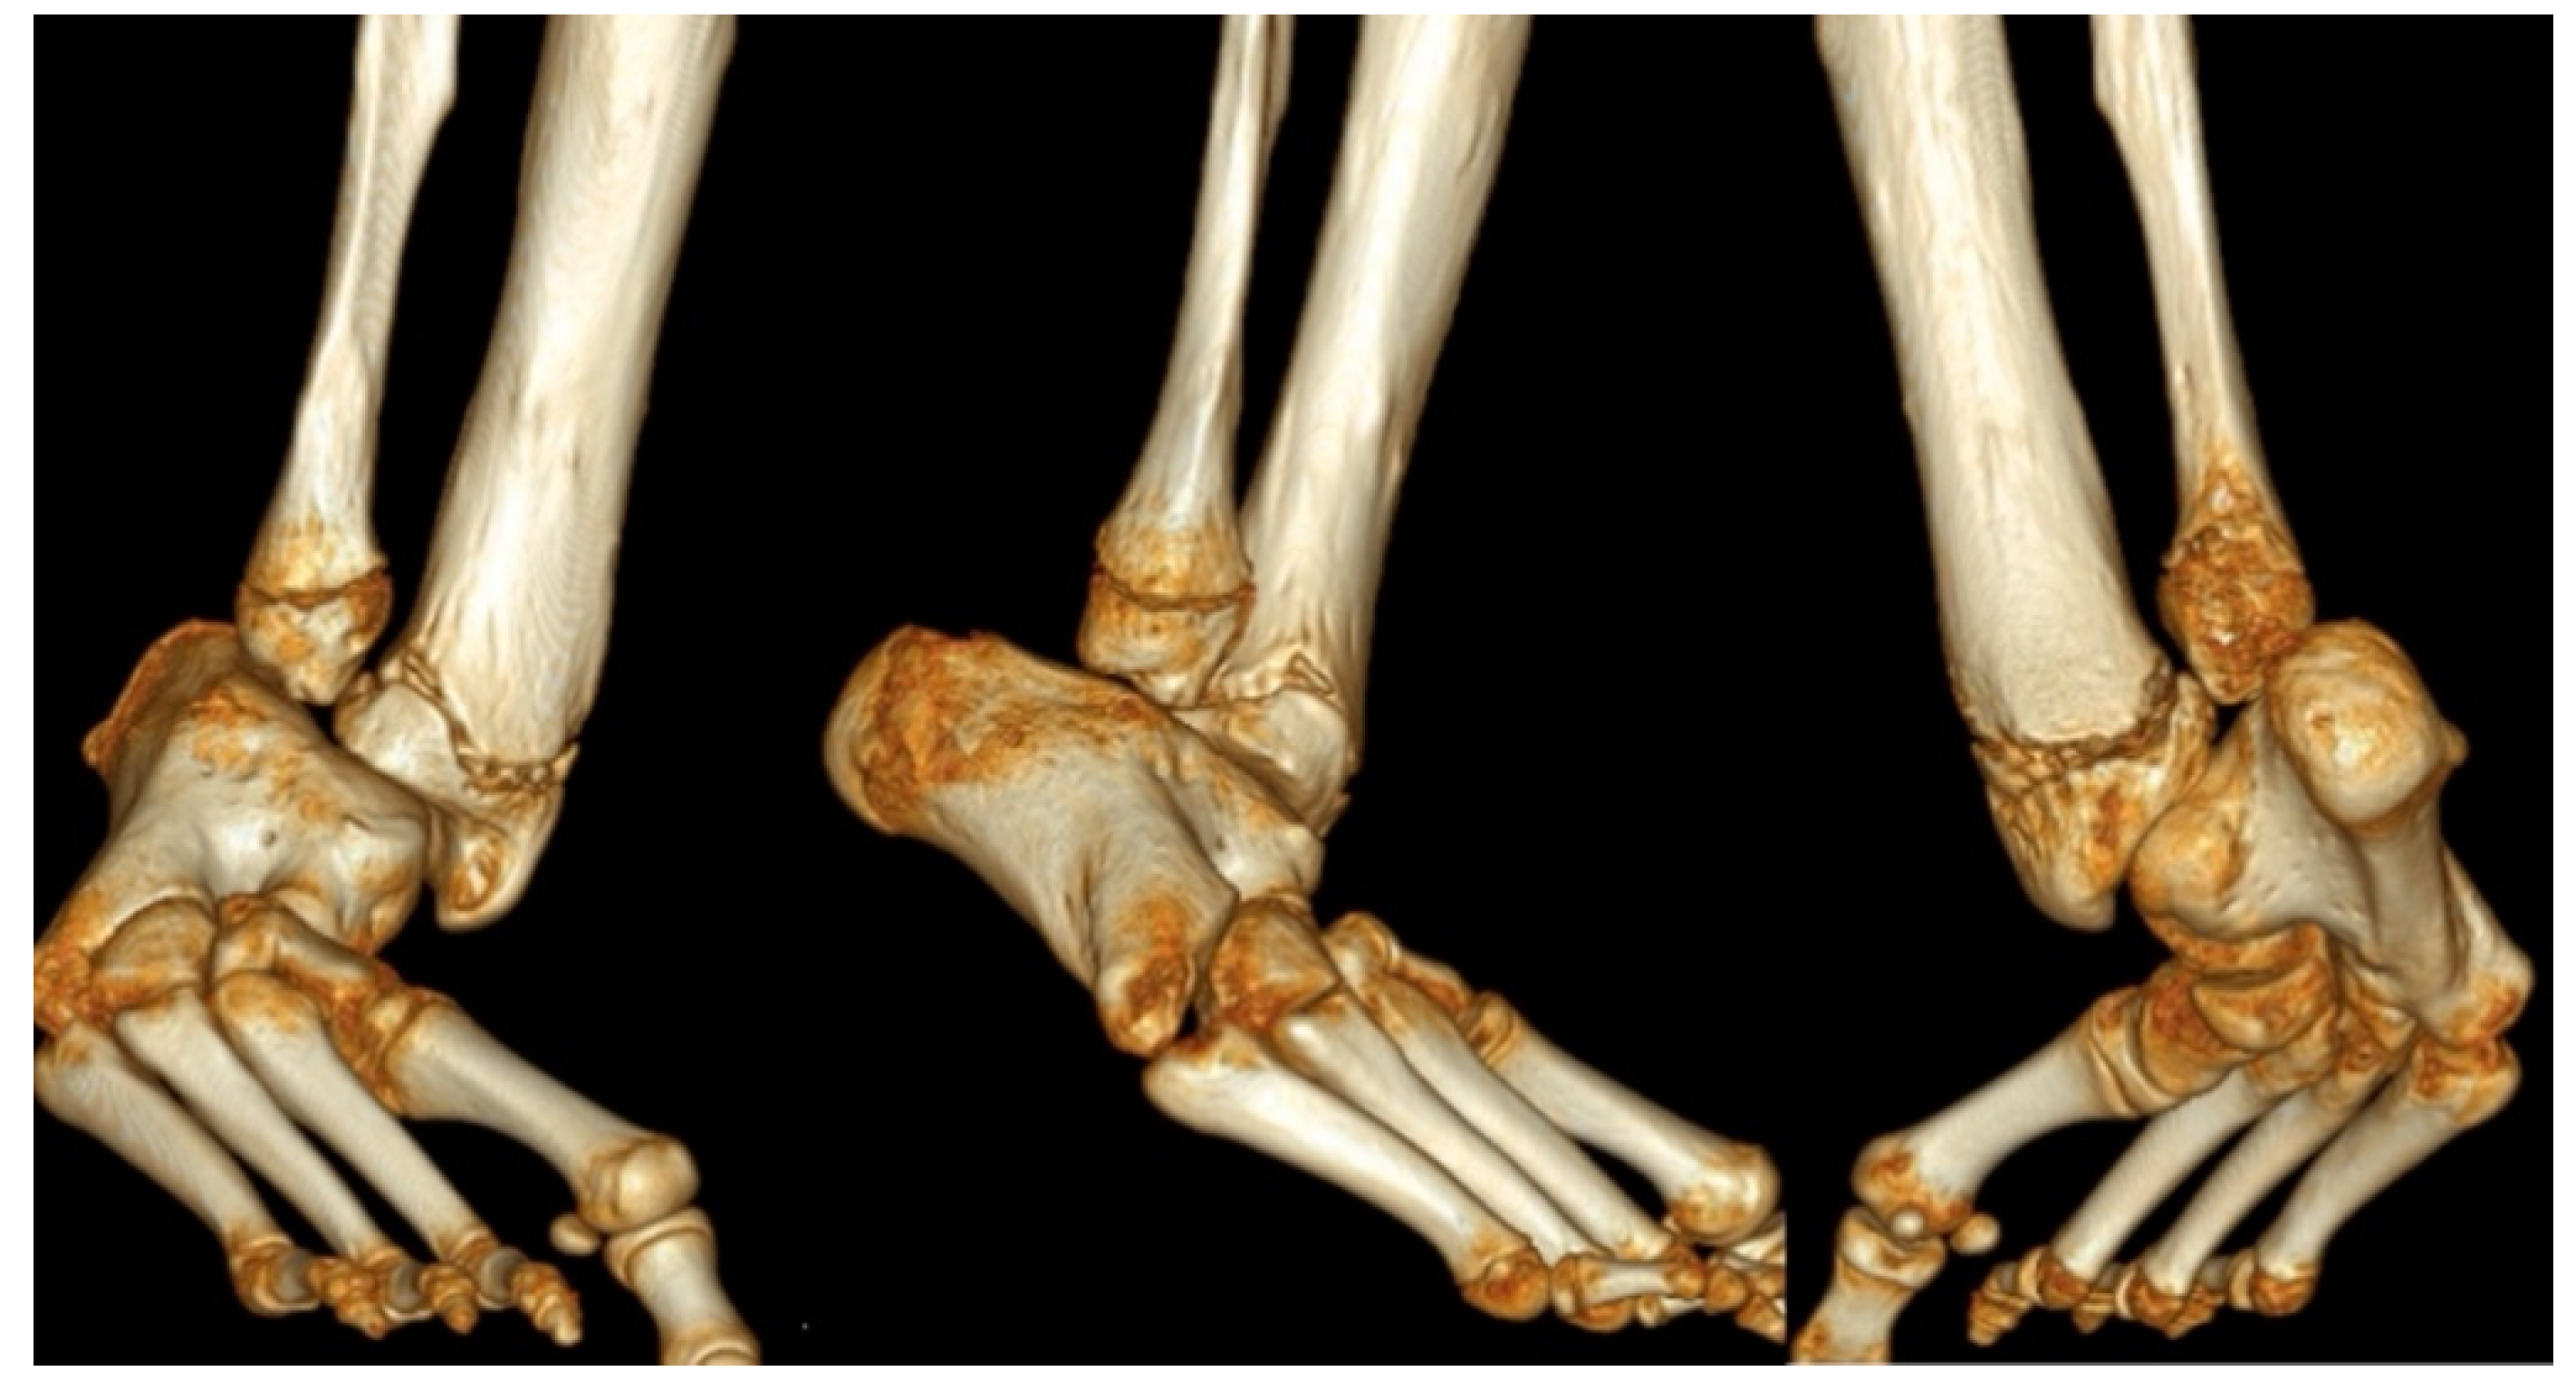

Figure 3.

A three-dimensional CT scan of distal tibia and foot (left Anteroposterior (AP) view, middle lateral view and right posteroanterior (PA) views) in a 13-year-old boy with untreated type 3c fibular hemimelia with fixed equino-valgus of the hindfoot. Despite the presence of a fibula, there is valgus-procurvatum malorientation of the ankle plafond, and a malunited subtalar coalition. The calcaneus is articulating with the fibula. There are also calcaneo-cuboid and talo-navicular coalitions with midfoot adductus.